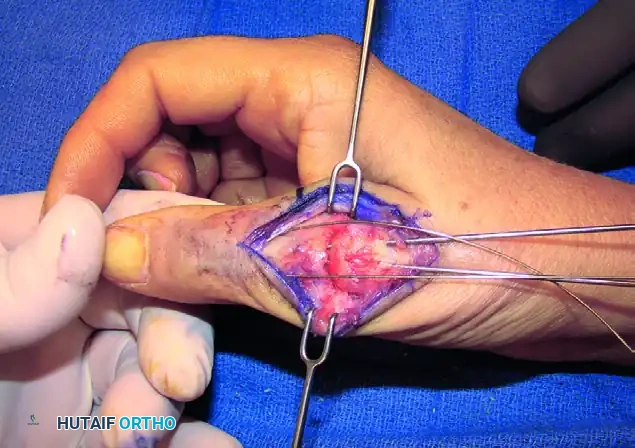

5. Kirschner Wire Placement and Construct Initiation

With the joint held in the optimal position, the tension band construct is initiated.

- Drill a transverse hole through the distal third of the proximal phalangeal neck using a 1.1 mm (0.045-inch) K-wire. This hole will serve as the distal anchor for the tension band wire.

- Pass a 24-gauge or 26-gauge stainless steel orthopedic wire through this transverse hole.

- Next, drive two longitudinal 1.1 mm or 1.6 mm (0.045-inch or 0.062-inch) K-wires in a retrograde fashion. Start at the dorsal base of the proximal phalanx, cross the prepared MCP joint interface, and advance into the metacarpal shaft. Ensure these wires cross proximal to the fusion site to provide rotational stability.

FIGURE 73-40E: Placement of a Kirschner wire in the distal third of the proximal phalangeal neck, completing the foundation of the tension band construct.